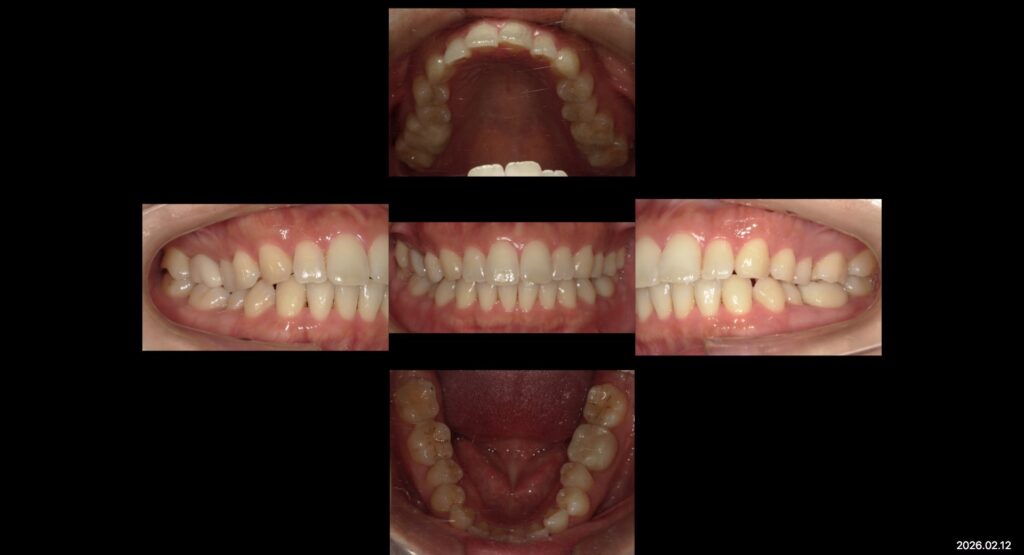

治療前↑

治療後↑

●治療内容

右上6e-maxCr

右上7e-maxOn

左下6e-maxCr

マウスガード作成

虫歯治療。予後のいい補綴治療。マウスガード作成で咬合力から歯を守る。